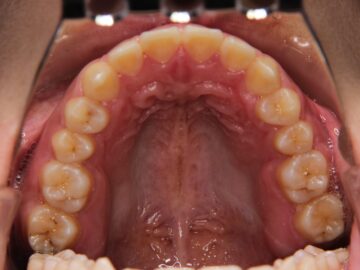

ご相談時

治療後

上下顎全体にブラケットを装着し、隙間を閉じることを勧めた。